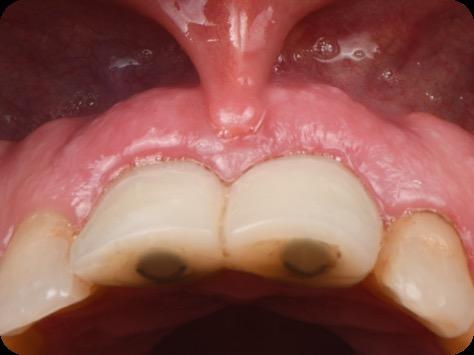

Restoring incisal wear and closing diastema with G-aenial A’CHORD. Courtesy of: Dr Aleksandra Slacan, Poland